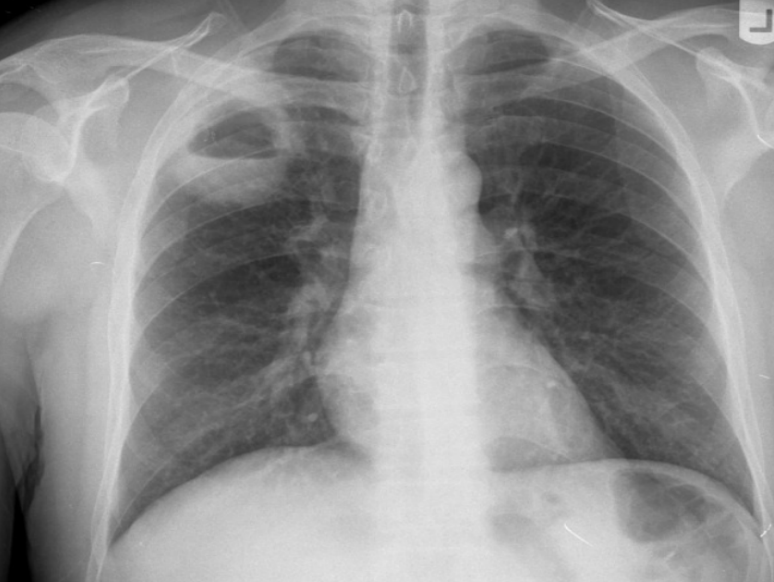

radio-opacity on right upper lung zone

right hilum lifted upward

trachea divated to ipsilateral side (to the right)

Ddx: atelectasis/lung collapse, lung fibrosis, iatrogenic (lobectomy)

sharp line of demarcation of right upper lobe opacity (everything below is normal)→right upper LOBE collapse

causes of collapse→anything obstructing rught upper lobe bronchous; tumor, mucus blood.

tinted right hemidiaphragm (can also be seen in upper lobe collapse)